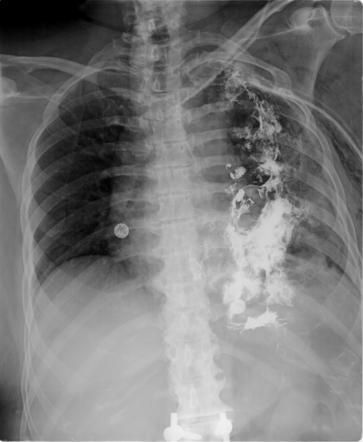

Forceful vomiting or retching can rupture the esophagus, resulting in a syndrome called Boerhaave syndrome. The patient may present with the following signs and symptoms: - Vomiting - Chest pain - Subcutaneous emphysema - Pain in the upper abdomen - Dyspnea - Pain in the back - Shock On radiography, pneumomediastinum, left pleural effusion, and left pneumothorax may be present. gas may be demonstrated in spaces in soft tissue of chest and neck. The gold standard treatment of boerhaave syndrome is surgery. A more conservative approach is esophageal stenting. Reference: https://radiopaedia.org/articles/boerhaave-syndrome